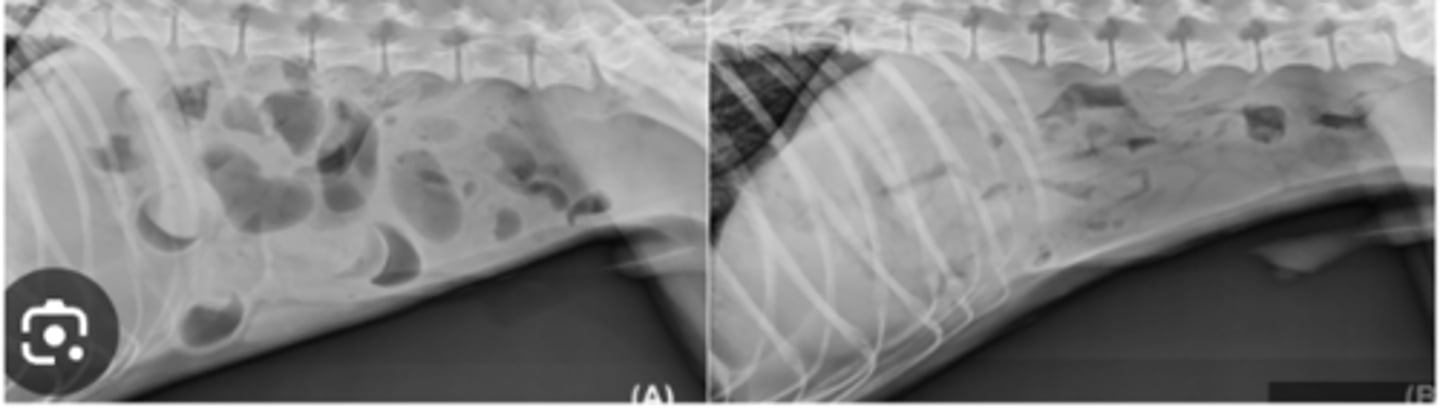

bronchial

What lung pattern is this?

What Lung pattern of young cat with respiratory signs is this?